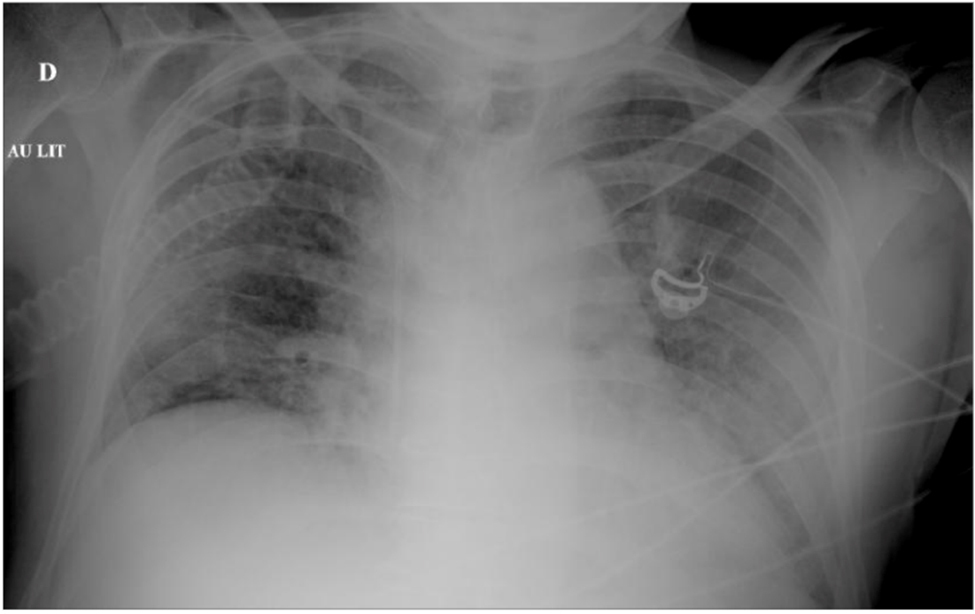

– l’infarctus du myocarde (facteurs de risque cardiovasculaire ++) ;

– l’anévrysme de l’aorte compliqué (syndrome fissuraire).